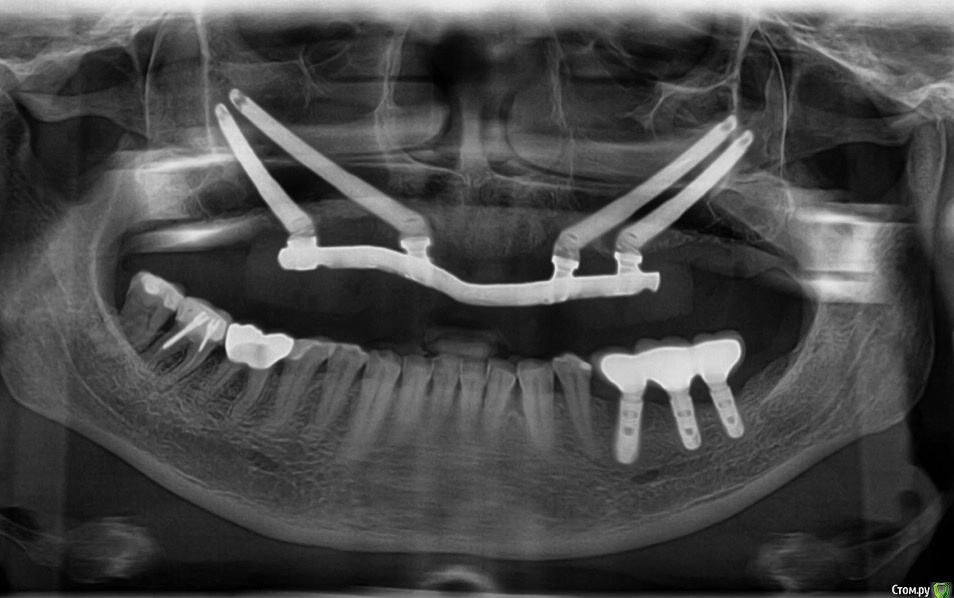

АнтонТЛТ Опубликовано 2 апреля, 2017 Поделиться Опубликовано 2 апреля, 2017 Выкладывайте оптг Ссылка на комментарий

Maggie78rus Опубликовано 2 апреля, 2017 Автор Поделиться Опубликовано 2 апреля, 2017 (изменено) Выкладывайте оптгСпасибо. Я первое фото с зеркалом не развернула Изменено 2 апреля, 2017 пользователем Maggie78rus Ссылка на комментарий